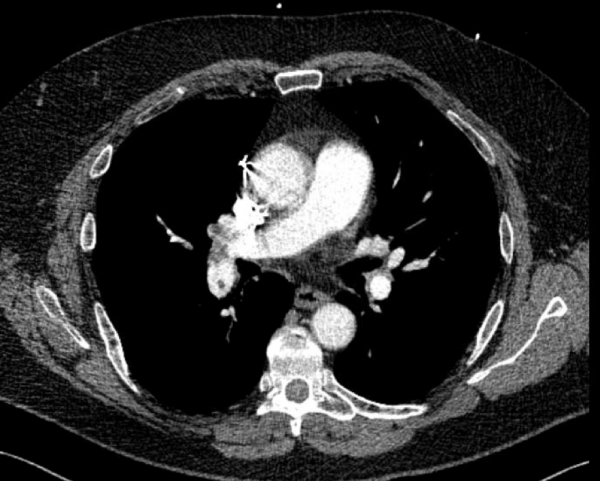

CT angiography of the chest with intravenous contrast was performed.

There is a filling defect straddling the bifurcation of the pulmonary trunk extending into the distal branches of the right lower, right middle, right upper and left upper lobe consistent with a saddle embolism. Bedside echocardiography revealed mild concentric hypertrophy, an ejection fraction of 60%, with normal right ventricular global systolic function, with no evidence for an elevated right ventricular systolic pressure.